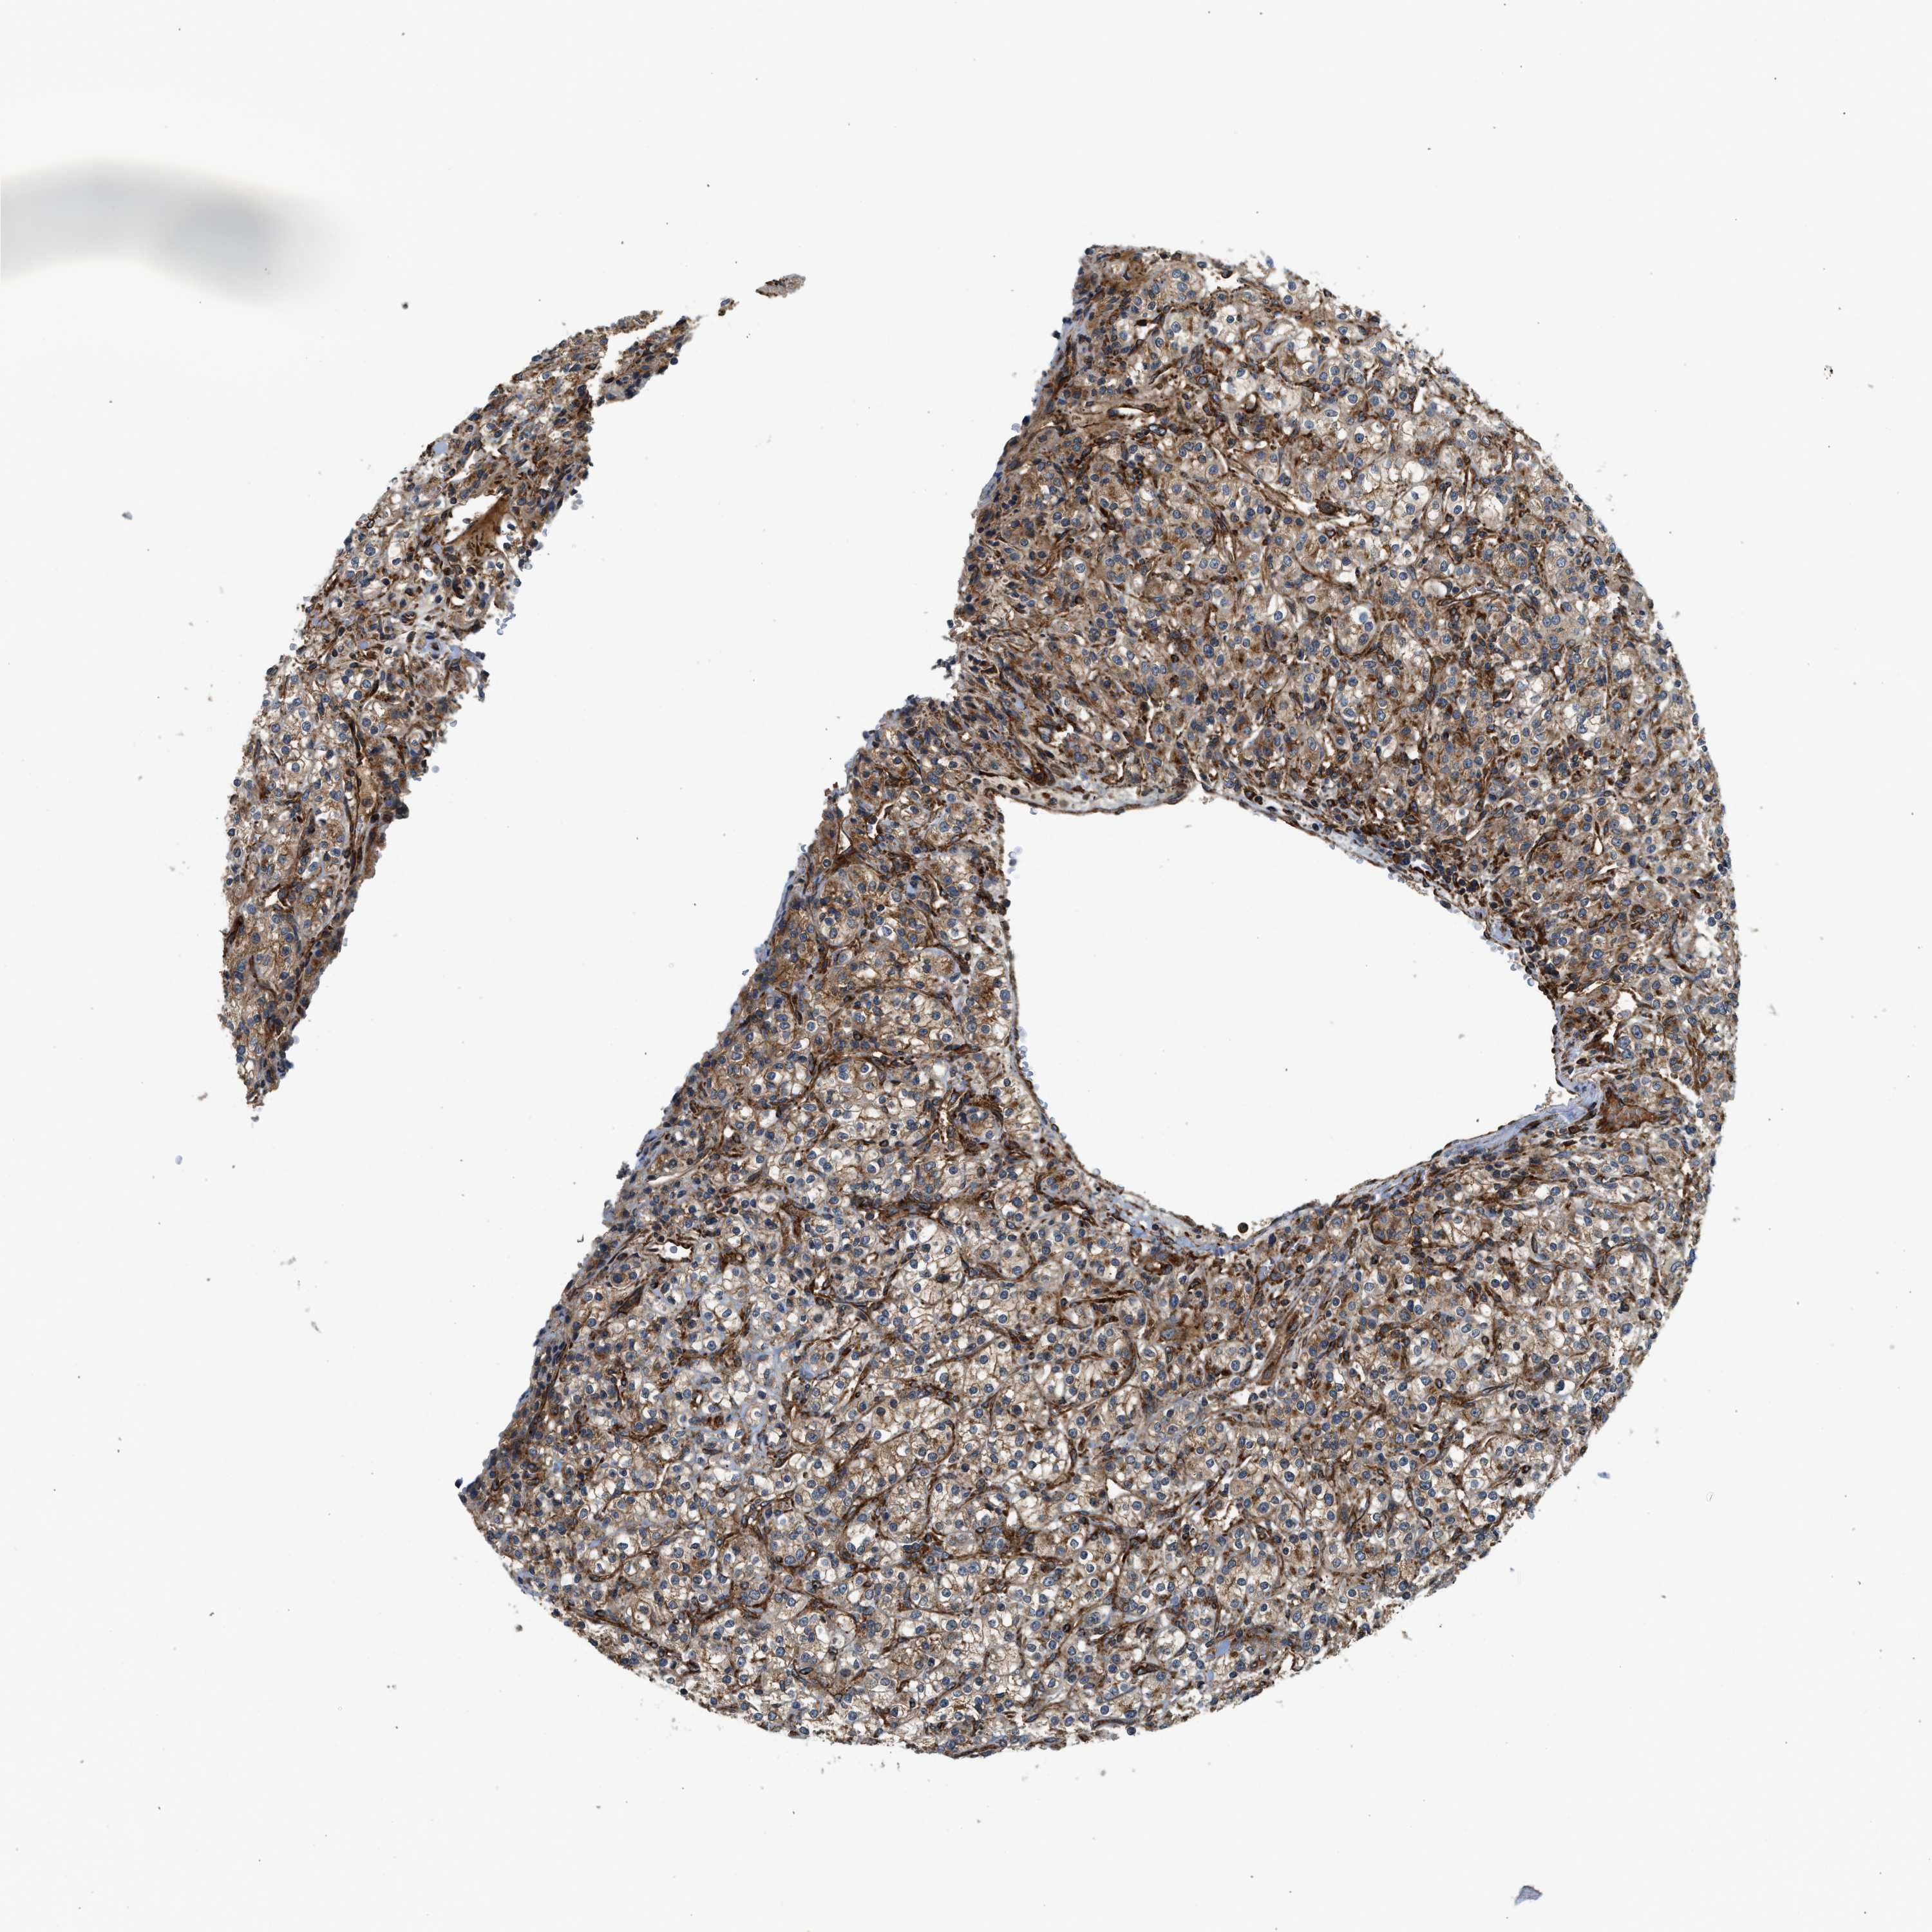

KIDNEY RENAL CLEAR CELL CARCINOMA (VALIDATION) - Interactive survival scatter ploti

The Survival Scatter plot shows the clinical status (i.e. dead or alive) for all individuals in the patient cohort, based on the same data that underlies the corresponding Kaplan-Meier plots. Patients that are alive at last time for follow-up are shown in blue and patients who have died during the study are shown in red.

The x-axis shows the expression levels (FPKM) of the investigated gene in the tumor tissue at the time of diagnosis. The y-axis shows the follow-up time after diagnosis (years). Both axes are complimented with kernel density curves demonstrating the data density over the axes. The top density plot shows the expression levels (FPKM) distribution among dead (red) and alive patients (blue). The right density plot shows the data density of the survived years of dead patients with high and low expression levels respectively, stratified using the cutoff indicated by the vertical dashed line through the Survival Scatter plot. This cutoff is automatically defined based on the FPKM cutoff that minimizes the p-score. The cutoff can be changed by dragging the vertical line or by entering a cutoff value in the square labeled "Current cut-off".

Under the Survival Scatter plot the p-score landscape (black curve; left axis) is shown together with dead median separation (red curve; right axis). Dead median separation is the difference in median mRNA expression between patients who have died with high and low expression, respectively. It is calculated as follows: median FPKM expression of dead patients with high expression - median FPKM expression of dead patients with low expression. This is intended to aid the user in visually exploring custom cutoffs and the associated p-scores and dead median separation.

Individual patient data is displayed and can be filtered by clicking on one or more of the category buttons on the top of the page. Categories describing expression level and patient information include: high, low, alive, dead, female, male and tumor stages. The scale of the x-axis can be toggled between linear and log-scale by clicking on the "x log" button. Mouse-over function shows TCGA ID, patient information and mRNA expression (FPKM) for each patient.

& Survival analysisi

Kaplan-Meier plots summarize results from analysis of correlation between mRNA expression level and patient survival. Patients were divided based on level of expression into one of the two groups "low" (under cut off) or "high" (over cut off). X-axis shows time for survival (years) and y-axis shows the probability of survival, where 1.0 corresponds to 100 percent.

HIP1 is validated prognostic, high expression is favorable in Kidney Renal Clear Cell Carcinoma (validation)

Best expression cut offi

Based on the FPKM value of each gene, patients were classified into two groups and association between prognosis (survival) and gene expression (FPKM) was examined. The best expression cut-off refers the FPKM value that yields maximal difference with regard to survival between the two groups at the lowest log-rank P-value. Best expression cut-off was selected based on survival analysis .

When clicking on this number, the vertical dashed line indicating cut-off, the interactive survival plot, and the Kaplan-Meier curve will be adjusted to show results based on the best expression cut-off.

: 19.11

TCGA RNA samplesi

RNA-seq data is reported as average FPKM (number Fragments Per Kilobase of exon per Million reads), generated by the The Cancer Genome Atlas (TCGA) .

Normal distribution across the dataset is visualized with box plots, shown as median and 25th and 75th percentiles. Points are displayed as outliers if they are above or below 1.5 times the interquartile range. FPKM values of the individual samples are presented next to the box plot.

Average pTPM 17.6

Number of samples 100